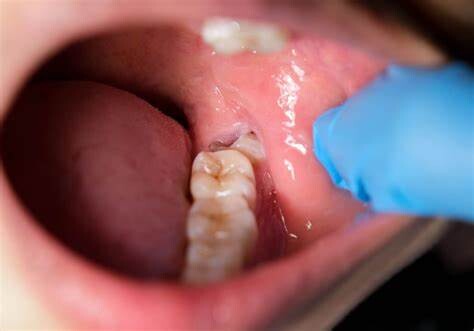

Formation of Cysts or Tumours

If the wisdom teeth problems are not dealt in an appropriate manner, the tooth will develop a sac within the jawbone. This sac has the ability to fill with fluid, which gradually develops into the formation of cyst, damaging the teeth, jawbone, and nerves. There are chances that this cyst could progressively develop into a tumour if untreated which could ultimately result in the removal of tissue and jaw bones.

Mutilates the Neighbouring Teeth

Since there is not enough room for the tooth to grow, it will case the teeth to grow in an abnormal manner. This results in impaction of the teeth, giving rise to many other oral problems. When the wisdom tooth emerges against the second set of molar, it might damage them, increasing the risk of acute infection. It will also have an effect on other teeth, which will intensify the need for an orthodontic treatment to align the other teeth.

Tooth Decay

The fully impacted or the partially impacted wisdom teeth are at greater risk of tooth decay, than other teeth. This usually happens, because of the location of the wisdom tooth, especially towards the back of the mouth, which is hard to clean. Moreover, since it lies at the back of the mouth, there are chances of food getting easily trapped between the gums and the tooth, promoting the growth of bacteria.

You can’t prevent the occurrence of an impacted wisdom tooth, but with a regular dental check-up, your dentist will help you monitor the emergence of the wisdom tooth, with the help of dental X-rays and advanced methodologies, which might indicate the need of wisdom teeth removal.